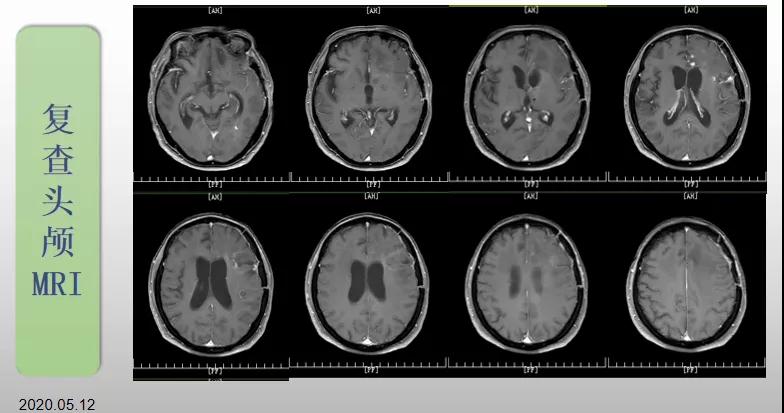

綜合治療 電場(chǎng)治療助70歲患者回歸正常生活

70歲的郝女士去年曾在外院查出“左額島葉”膠質(zhì)母細(xì)胞瘤(WHO Ⅳ級(jí)),并做了左側(cè)額島葉占位性病變切除術(shù)。術(shù)后進(jìn)行了同步放化療。由于治療條件有限,郝女士慕名來(lái)到我院就診。賀世明主任率領(lǐng)醫(yī)護(hù)團(tuán)隊(duì)立即為郝女士進(jìn)行了全面的檢查,決定為其進(jìn)行綜合治療 電場(chǎng)治療。經(jīng)過(guò)三個(gè)多月的綜合治療,患者復(fù)查頭顱MRI病變較前明顯縮小。出院時(shí),郝女士神志清醒,睡眠飲食正常,說(shuō)話很流利。“我是躺著進(jìn)來(lái)的,現(xiàn)在不用人攙扶,自己就可以走出病房了?!焙屡坷t(yī)護(hù)人員的手說(shuō)。